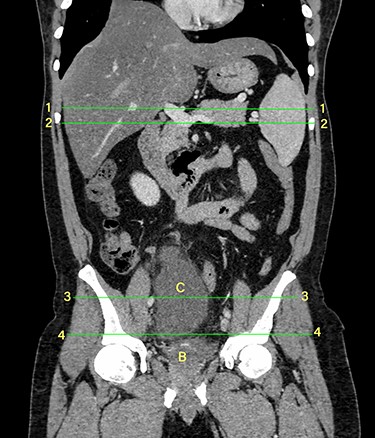

Computerized tomography showed a solitary well defined intraperitoneal cyst consisting of fluid showing low attenuation. The wall of the cyst was 1 cm thick, with no contrast enhancement. It was situated in the pelvis compressing the urinary bladder. It had no communication with either the bowel or the urinary bladder. The pancreas was normal, as also the rest of the abdominal organs. There was no ascites (Figs. 1–5). The diagnosis was a large intraperitoneal infected cyst.

Transverse section image of a contrast-enhanced CT scan of the abdomen at the level 3–3 (Fig. 1), showing a solitary cyst (arrow) with a non-enhancing wall separate from the intestines.

Transverse section image of a contrast-enhanced CT scan of the abdomen at the level 4–4 (Fig. 1), showing a solitary cyst (C) with a non-enhancing wall separate from the urinary bladder (B). Iliac vessels are labelled with arrowheads.